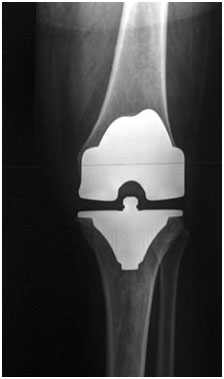

X-ray of total knee replacement, anterior-posterior (front to back) view.